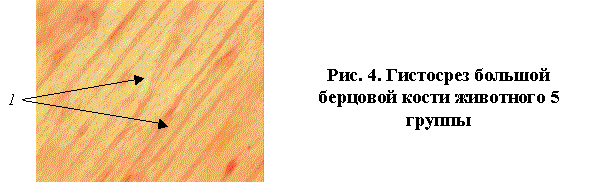

В образцах костей животных 5 группы костная ткань

была представлена губчатой и компактной структурами с умеренно

склерозированными трабекулами. В зоне введения фиксаторов было заметно наличие

очагов подострого воспаления, при этом отмечалось присутствие молодого

волокнистого хряща, что свидетельствует о формировании молодой костной ткани 1

и наличии выраженных остеокондуктивных свойств у покрытий, полученных при

температуре воздушно-термического оксидирования 6000С (рис.4).